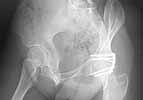

I would like to present to you a case of a young woman (born 1976) with a acetabular fracture of the posterior wall. In first instant missed in another hospital, operated after 3 weeks in Januari 1997. Standard prone position KL approach, Ischial nerve was not involved as far as we could determine preop and perop. The Ischial nerve was observed, not extensively explored. Standard ORIF and postop mobilization without problems. Postop no neurological complaints and normal function and strength, followup in the other hospital. After 5 years suddenly pain in the trochanteric region, probably a bursitis trochanterica, nonoperative treatment with Lidocaine Kenacort injections. Radiolgy and bonescintigraphy showed no changes or hotspots, no signs of joint narrowing etc. After 2 injections the pain disappeared. Then fall/winter 2003-2004 she returned with pain higher in the buttock near the distal part of the SI joint same side as her acetabular fracture. Irritation of the M. piriformis was the first diagnosis. Exercises and change of work, no result. Orthopedic consult: no joint problems.

She returned to my outpatient clinic: pain buttock and slight radiation lateral side of the leg in certain positions of pelvis/leg. Cannot stand on her leg for long periods: 3-4 hr. then pain buttock and leg. Slight atrophy of the gluteal muscles (4+). Gross neurological research: no deficits, reflexes normal, can stand on her toes. Xray of the pelvis: no joint space narrowing.

Does anybody have a suggestion?? Ischiadic nerve neuropathy due to HO or scar tissue? CT scan in 1998 (1 year postop) showed no heterotopic ossifications, but is hard to read due to scatter.